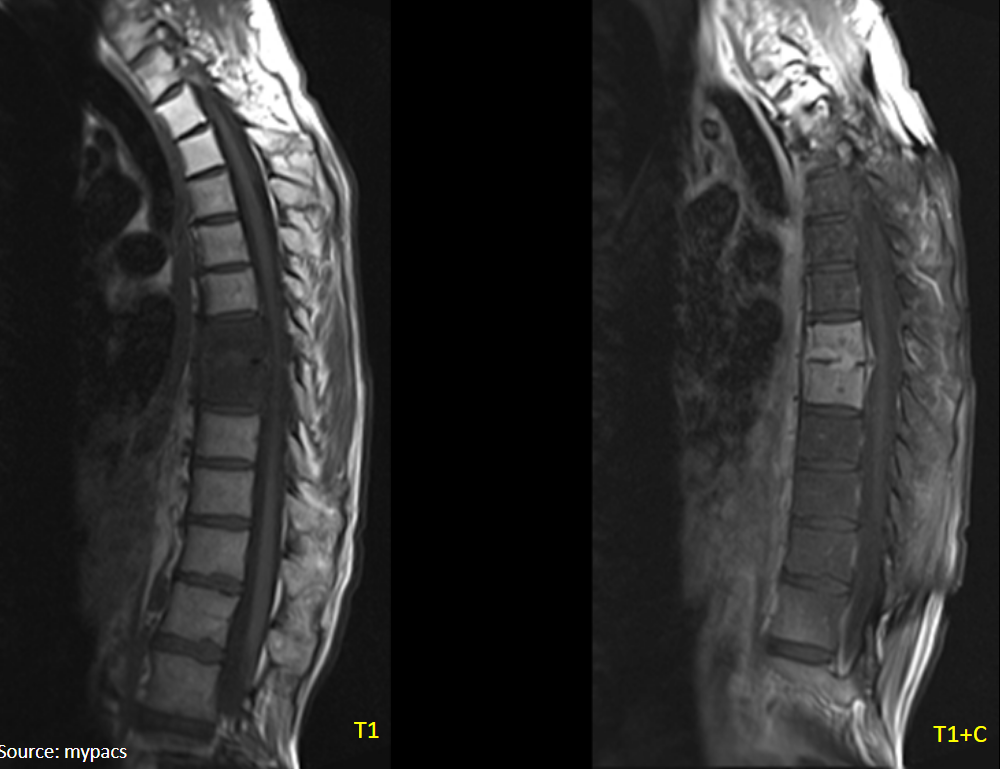

18

Q

This is spondylodiscitis.

Why is an infection in this area particularly dangerous?

A

Increased spinal pressure leading to inflammation:

• meningitis

• encephalitis

• neural infection

20

What is shown by the MRI with contrast?

What is the diagnosis?

Phlegmon

Spondylodiscitis

pus has more protein